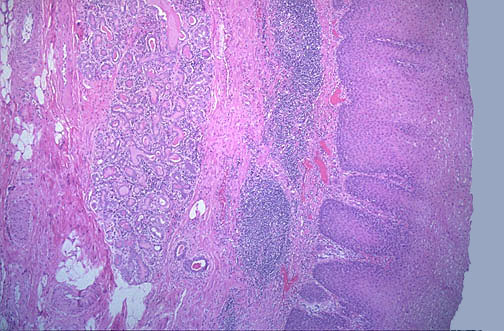

Normal non-keratinizing esophageal

squamous mucosa

has an underlying

submucosa

to the left containing

mucus glands

, along with

lymphoid tissue

.